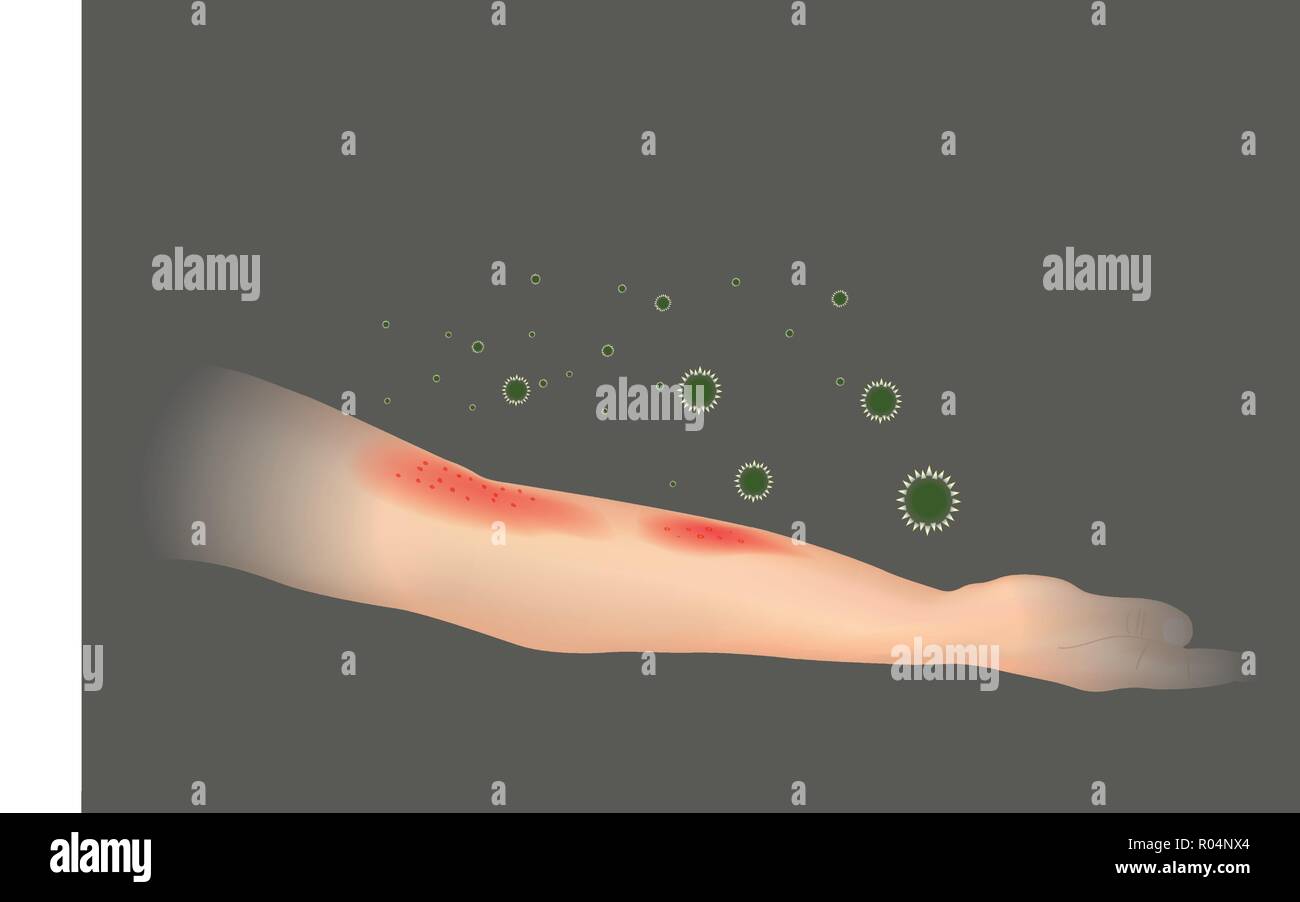

Allergia della pelle. La comparsa di eruzioni cutanee in braccio. Illustrazione. Illustrazione Vettorialehttps://www.alamy.it/image-license-details/?v=1https://www.alamy.it/allergia-della-pelle-la-comparsa-di-eruzioni-cutanee-in-braccio-illustrazione-image223839788.html

Allergia della pelle. La comparsa di eruzioni cutanee in braccio. Illustrazione. Illustrazione Vettorialehttps://www.alamy.it/image-license-details/?v=1https://www.alamy.it/allergia-della-pelle-la-comparsa-di-eruzioni-cutanee-in-braccio-illustrazione-image223839788.htmlRFR04NX4–Allergia della pelle. La comparsa di eruzioni cutanee in braccio. Illustrazione.